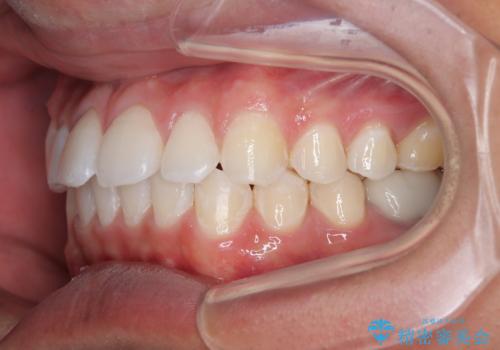

矯正治療後は、奥歯の銀歯をセラミッククラウンにて補綴治療を行うこととしました。

あっという間に歯列が整い、目立っていた銀歯もなくなり、清潔感のある口元になりました。